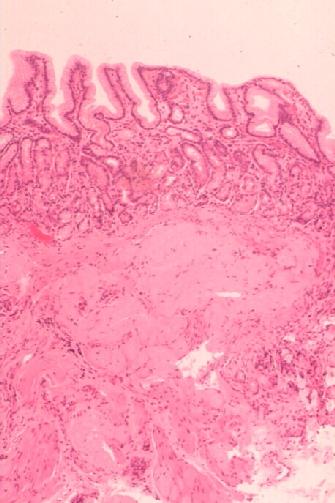

OMH 981706; Amyloidosis, stomach (HE stain [jpg.29KB]), (Congo red stain [jpg.37KB])

2. The heart is enlarged and abnormally stiff, which weighs 700 gram and, on cross sections, reveals marked dilatation of both the atriums and hypertrophy of both the ventricles, but no scarring of the myocardium is noted ([jpg.21KB]). The lumen of the left ventricle is moderately dilated. Fresh coagulation mass, partly thrombotic, is adherent to the wall of the right auricle. The circumferences of all the four valves are remarkably increased, resulting in insufficiency state. Arteriosclerotic changes of the coronary arteries are minimal to the naked eye, without narrowing. Microscopic examination reveals patchy and diffuse deposition of amorphous eosinophilic extracellular substance (HE stain [jpg.45KB]) that is stained pink or orange by Congo red stain and shows rather moderate birefringence by polarizing microscopy ([jpg.13KB]). Myocardial fibers show atrophy and degeneration.

b. The esophagus, stomach and intestines are otherwise unremarkable to the naked eye than mild mucosal petechia of the stomach with bloody content that measures about 100 ml in volume. Microscopic examination reveals diffuse and patchy deposition of amyloid substance mainly in the smooth muscle layer but also in the muscularis mucosae and submucosa of those organs (Sigmoid, HE stain [jpg.26KB]).